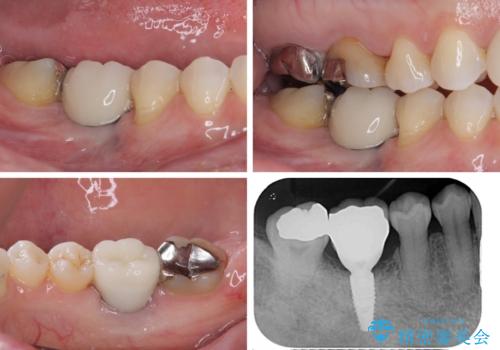

上下非接触の咬み合わせは、舌突出癖によるところが大きく、トレーニングを行いながら治療を進めていきました。

なかなか突出癖が改善できず、過剰歯を抜歯したスペースを閉じるまでに時間がかかりました。

舌突出癖の改善は、治療期間や仕上がりに大きな影響を与えるため、しっかりとトレーニングすることが大切です。

咬み合わせ改善のため、前歯の過剰歯を抜去し、ワイヤー矯正にて歯列と咬み合わせることとしました。

左上の奥歯のブリッジや前歯のセラミッククラウンはいったん除去し、矯正治療後に補綴治療を行うこととしました。

また、右下の抜歯が必要な奥歯は、矯正治療の途中でインプラントを埋入し、矯正治療後に上顎と合わせて補綴治療を行うこととしました。